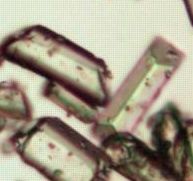

3. 종류

요로결석은 소변 내 미네랄이 응고되어 만들어지는 결정체이다. 결석은 주로 신장이나 방광에 형성되며, 각각 신장결석증과 요석증으로 불린다.

요로결석은 구성 성분에 따라 다음과 같이 분류된다.

전 세계적으로 가장 흔한 결석은 칼슘 결석이다. 미국에서는 신장결석의 약 80%가 칼슘 결석이며, 주로 옥살산칼슘 또는 인산칼슘과의 혼합물 형태로 나타난다.

요로결석은 요로계 어디에서든 발생할 수 있다. 신장에 결석이 있으면 신장결석증(nephrolithiasis), 요관에 있으면 요관결석증(ureterolithiasis)이라고 한다. 방광에 형성되거나 통과하는 결석은 방광결석(bladder stone)이라고 한다.

요로결석 성분 발견율은 다음과 같다.[89]

| 요로결석 성분 | 발견율 |

|---|---|

| 수산칼슘과 인산칼슘의 혼합 | 44.3% |

| 인산칼슘 | 16.8% |

| 수산칼슘일수화물 | 12.2% |

| 요산 | 7.6% |

| 수산칼슘일수화물과 이수화물의 혼합 | 6.9% |

| 수산칼슘이수화물 | 6.1% |

| 인산마그네슘암모늄 | 3.8% |

| 시스틴 | 2.3% |

소변의 pH에 따라, 인산칼슘 및 인산암모늄마그네슘 결정은 알칼리성에서, 요산 및 수산칼슘 결정은 산성에서 많이 나타난다.[90]